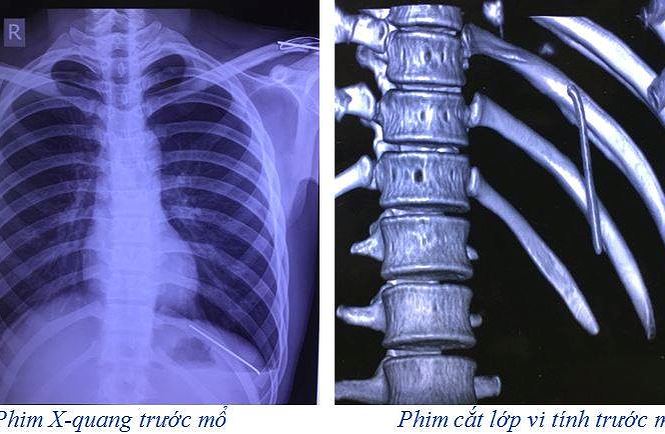

30/05/2019 16:45Thanh niên 18 tuổi bị đinh dài 7 cm 'du lịch' từ vai xuống tận phổi

Người bệnh H nhập viện trong tình trạng đau vùng đáy phổi trái, đau thượng vị lan ra sau lưng kèm theo khó thở nhẹ, thông khí phổi trái giảm, không đau vai trái, cử động tay trái bình thường. Tiền sử: đã phẫu thuật kết hợp xương đòn trái bằng 2 đinh kirschner cách 7 tháng.

Sau khi thăm khám, các bác sĩ đã chỉ định chụp X-quang và cắt lớp vi tính lồng ngực. Kết quả phim cắt lớp vi tính lồng ngực cho thấy: dị vật dạng kim khí trong KMP trái, tràn khí KMP trái.

Nguyên nhân là do chiếc đinh đó di chuyển từ vị trí xương đòn trái theo thời gian nó rơi tự do vào trong khoang màng phổi trái. Trước khi mổ ca bệnh này thì kíp phẫu thuật và kíp gây mê hồi sức đã chuẩn bị tối đa các phương án đề phòng nếu có tổn thươnghệ thống mạch máu lớn và tim. Rất may mắn là chiếc đinh chỉ làm rách nhu mô phổi gây tràn khí khoang màng phổi trái.